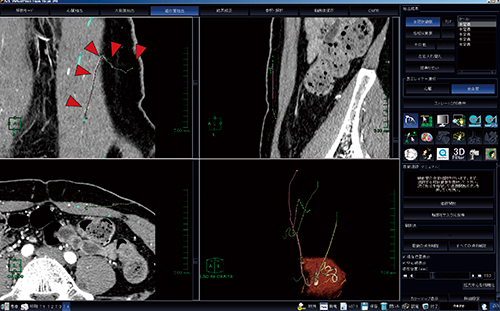

AZE VirtualPlace 雷神での穿通枝の抽出は,以下の手順で行う。まず,画像をCT細血管解析に取り込み,“解析モード”をマニュアルで実行する。次に,“大動脈抽出”では膀胱辺りに仮想点を設定する(図1)。“細血管抽出”は,左右総腸骨動脈から分岐している下腹壁動脈におのおの数点打ち,自動追跡を行う。自動追跡で下腹壁動脈本幹が抽出された後,穿通枝をマニュアルで抽出していく。本ソフトウェアでは各断面が1画面で表示されているため,同定しやすい断面で穿通枝にポイントを設定して抽出し,マスクの反映を行っていく。この方法であれば,皮下レベルの血管まで作成可能である。また,マスク反映した血管はカラー表示されるため,未抽出血管も一目でわかり,見落としなく作成することが可能である(図2,3)。

図1 血管解析までのワークフロー

CT細血管解析に画像を取り込み,解析モードをマニュアル(□)に設定する。大動脈抽出は,骨盤内に仮想点を打つ(○)。

図2 下腹壁動脈の自動抽出方法

細血管抽出において左右(図は左)の総腸骨動脈から複数のポイントを打ち,自動抽出を行う(◀)と,下腹壁動脈本幹が抽出される。抽出後,マスクされた血管は緑色で表示される(→)。